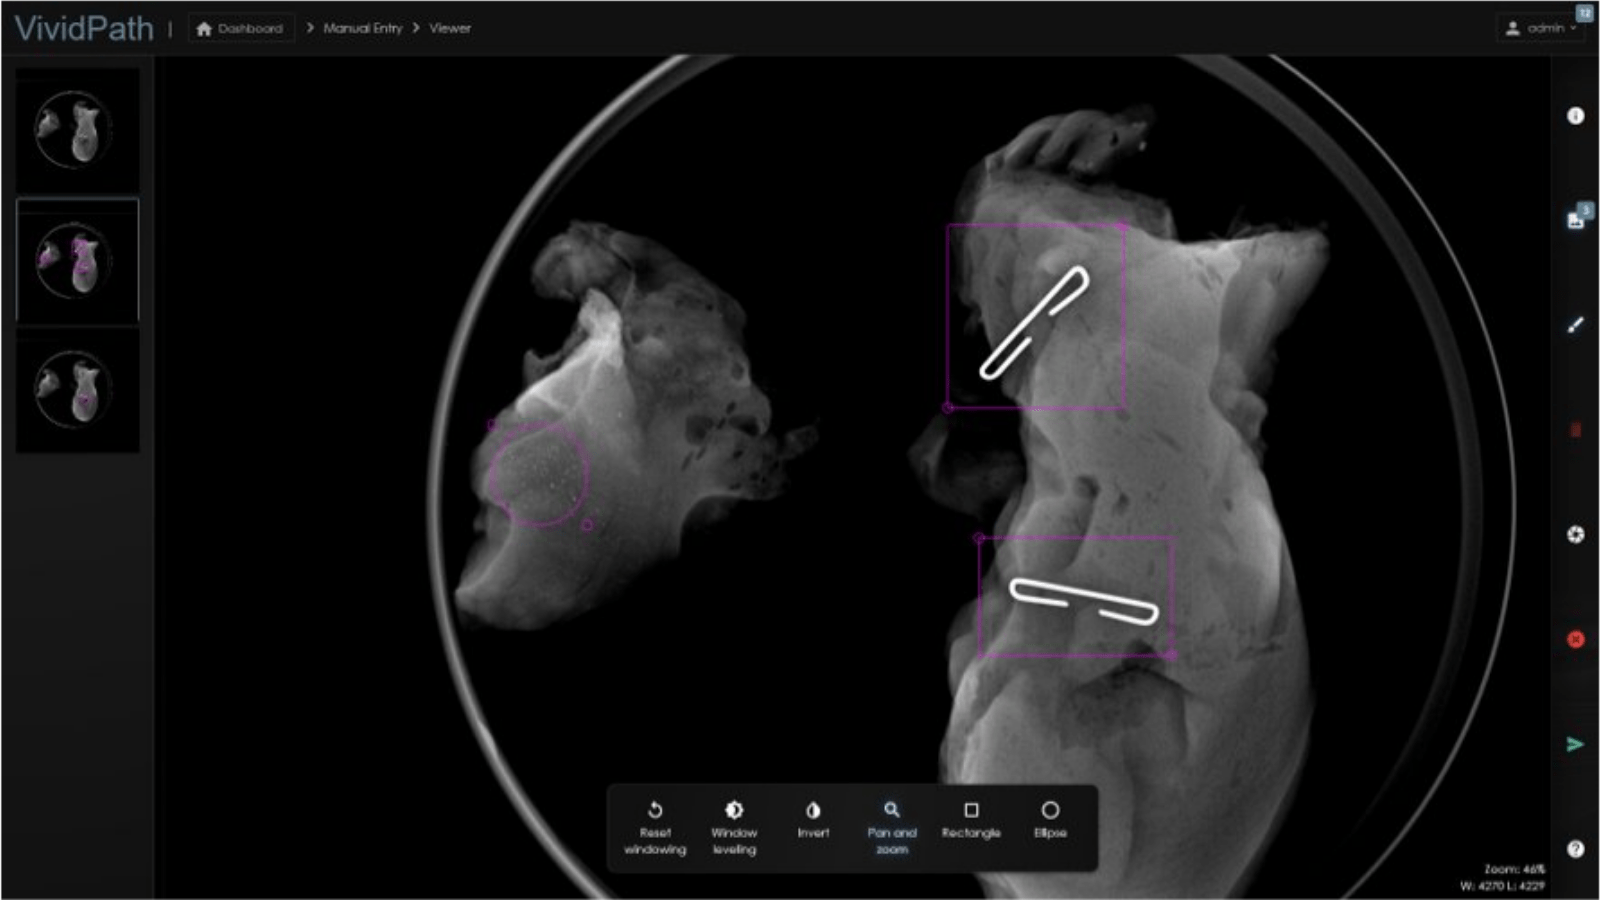

From www.hologic.com

Faxitron® Path+ Specimen Radiography System Hologic Specimen Radiograph Definition In breast conserving surgery (bcs), specimen mammography is one of the most widely used intraoperative methods of. Other techniques that may occasionally aid the surgical pathologist in tumor diagnosis. Localisation of the malignant lesions was. Review of specimen radiographs is one of the best ways to learn the differences in the appearance of benign and malignant lesions of the breast.. Specimen Radiograph Definition.